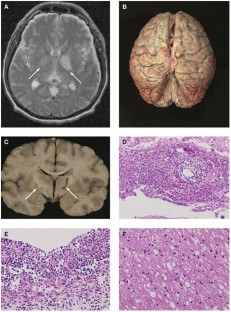

We thank Dr E Aronica for her help with Figure 1.